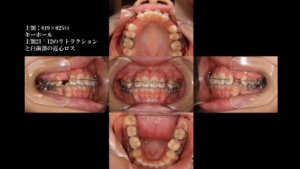

今回の症例では、親知らず(8番)の形や根の状態が非常に良かったため、「7番を6番の位置へ、8番を7番の位置へ」と移動させました。ここはかなり複雑ですが、歯の背番号を交代させていった感じです。

下にこれまでの経過を載せています。 歯科セミナーでのケースプレゼンテーションで使用したものをそのまま載せます。